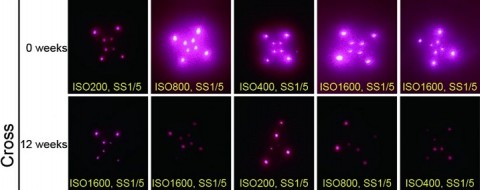

Na experiência, publicada na quarta-feira (18/12) no Science Translational Medicine, a equipe do MIT uso adesivos com microagulhas para depositar os pontos sob a pele de cobaias e depois conseguiu reconhecer a mensagem com uso de um smartphone, alterado para detectar luz quase infravermelha, invisível a olho nu. Os testes foram feitos também com corpos humanos de vários tons de pele. A mensagem persistiu por nove meses. Os cientistas acreditam que, no estágio atual da pesquisa, a mensagem se mantenha estável por cinco anos.

Pesquisadores liderados por uma equipe do Instituto de Tecnologia de Massachusetts (MIT) criaram uma plataforma de microagulhas usando micropartículas fluorescentes chamadas pontos quânticos (QD), que podem fornecer vacinas e, ao mesmo tempo, codificar invisivelmente o histórico de vacinas diretamente na pele. Os pontos quânticos são compostos de nanocristais, que emitem luz infravermelha próxima (NIR) que pode ser detectada por um smartphone especialmente equipado. Testes usando a plataforma mostraram que QDs entregues a amostras de pele humana ainda eram detectáveis após fotodegradação que simulavam cinco anos de exposição à luz solar e permaneceram detectáveis por até nove meses quando testados em ratos.

A detecção dos micropontos é possível usando smartphones especialmente adaptados que podem detectar a fluorescência no infravermelho próximo. "Como esses telefones oferecem capacidade de processamento a bordo, aplicativos de câmera e módulos de câmera de baixo custo para consumidores, optamos por adaptar um smartphone existente para permitir a criação de imagens NIR em vez de criar um sistema de criação de imagens completamente novo", escreveram eles. "Além disso, acreditamos que a familiaridade com a função desses dispositivos diminuirá a curva de aprendizado das imagens NIR em um ambiente de campo".

Ao carregar seletivamente micropartículas nas microagulhas, os adesivos proporcionam um padrão na pele invisível a olho nu, mas podem ser digitalizados com um smartphone que remove o filtro infravermelho. O adesivo pode ser personalizado para imprimir diferentes padrões que correspondem ao tipo de vacina entregue. Testes usando pele de cadáver humano mostraram que os padrões de pontos quânticos poderiam ser detectados pelas câmeras dos smartphones após cinco anos de exposição solar simulada. Os pesquisadores também testaram a estratégia de vacinação em ratos, usando adesivos de microagulhas que liberavam os pontos quânticos junto com uma vacina contra a poliomielite. Eles descobriram que esses ratos geraram uma resposta imune semelhante à resposta de ratos que receberam uma vacina tradicional contra a poliomielite injetada.